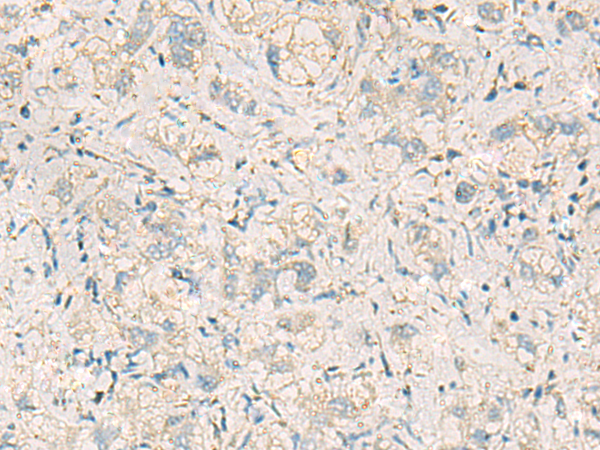

分类: 科研抗体货号: P10350别名: L9mt应用: IHC反应种属: Human, Mouse, Rat